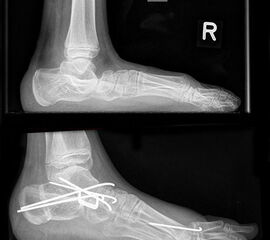

Bei jahrelanger Hackenfußfehlstellung sind teilweise auch knöcherne Korrekturen notwendig. Bei extrem fixierter Steilstellung des Calcaneus kommt es zu einem extremen Verlust des Hebelarms für die Wadenmuskulatur. Nur durch eine lateral-dorsal Verschiebung mit gleich­zeitiger Verkürzung der Wadenmuskulatur können dann die Hebelverhältnisse wiederher­gestellt werden. Häufig müssen solche Korrekturen mit einer komplexen Arthrodese von Rückfuß und Fußwurzel kombiniert werden um ausreichend stabile Verhältnisse zu erreichen. Gleichfalls sollten Varus- und Valgusdeformitäten durch Medial- oder Lateralverschiebung korrigiert werden 5.

Bei extremer Valgusdeformität des Rückfusses sollte das untere Sprunggelenk stabilisiert werden. Bei passiver Korrigierbarkeit bietet sich hierfür die Arthrorise an. Hierbei wird durch ein Implantat im Sinus tarsi die Rückfussvalgisierung blockiert. Nach Abschluss des Wachs­tums kann das Implantat wieder entfernt werden.

Bei kontrakter Fehlstellung des unteren Sprunggelenkes ist eine Arthrodese des Subtalar­gelenks indiziert (z.B. nach Green-Grice).

Gelingt es nicht die Dorsalextension über Sehnentransfers und ein Auftrainieren der Waden­muskulatur einzuschränken, besteht die Möglichkeit der ventralen Arthrorise mit Einbringen einem Knochenspan der auf der ventralen Tibia fixiert wird. Dieser wirkt als Stopper und blockiert die Dorsalextension in der gewünschten Gelenkstellung.